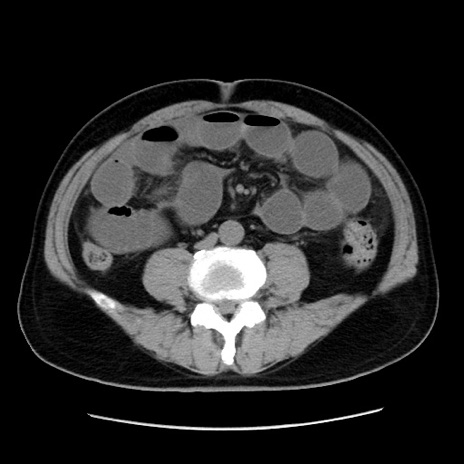

症例16(横断像)

【症例】 70歳代男性

【主訴】 腹痛、嘔吐

【現病歴】 約1ヶ月前より間欠的に腹痛と嘔吐あり、当院消化器内科を受診したところCTで多発する肝臓のLDAを指摘され、精査中であった。以降は消化器症状は安定していたが、2日前より嘔気と腹痛があり、同日より排便・排ガスが消失した。改善認めず、 本日、救急外来を受診した。

【既往歴】 大腸ポリープ切除後。

【身体所見】意識清明・会話良好、BT 36.3℃、BP 127/80mmHg、 P 80bpm、腹部:膨満あり、平坦・軟、上腹部正中および下腹部正中に圧痛あり、反跳痛なし、筋性防御なし。

【データ】WBC 7200、CRP 0.77